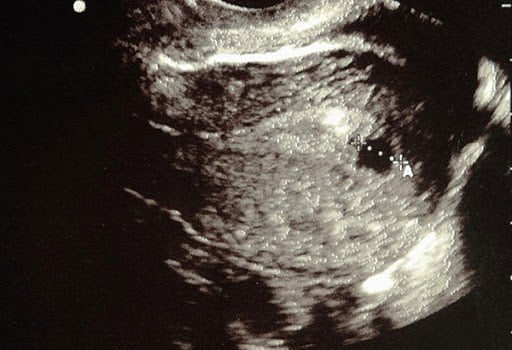

سونوگرافی هفته ششم بارداری

در هفته ششم بارداری، کودک شما تقریباً 1.8 – 1.4 اینچ طول دارد. تقریباً به اندازۀ یک دانه انار. او شبیه به یک بچه قورباغه به نظر می رسد. با یک دم کوچک که به ستون فقرات تبدیل خواهد شد. جوانه های ریزی در راه تبدیل شدن به دست، پا و گوش هستند. مغز، ریه ها و سایر اندام ها نیز در حال رشد هستند. اجزای صورت نیز در همین هفته شروع به شکل گیری می‌کند. دندان ها و یک لایه نازک از پوست وجود دارد. ضربان قلب کودک اغلب با سونوگرافی واژن در این مرحله از بارداری قابل تشخیص است.